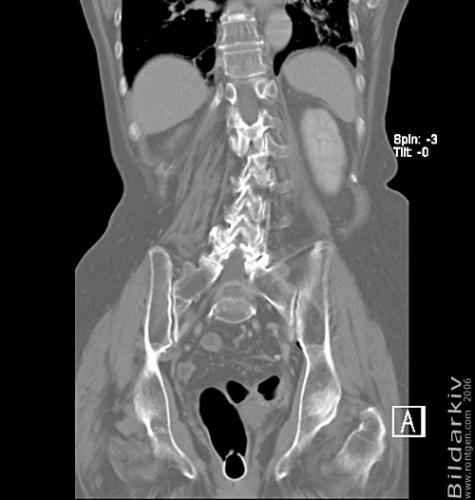

CT colon 38

Datortomografi av tjocktarmen (colon) med infunderad luft i tarmen samt med kontrast i blodbanan. Koronar bildserie.

CT multislice 16